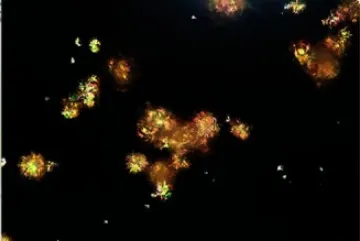

IRA + Icterícia: Um Caso que Exige Investigação Detalhada